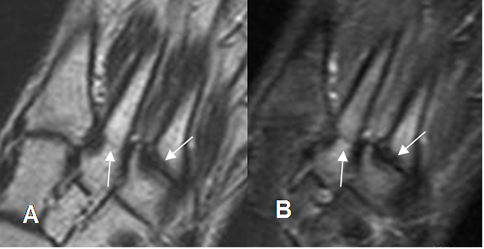

Fig 36 A. Fractura de stress.

A: RM coronal en T1 y B: RM coronal en STIR. Fracturas no desplazadas y de evolución aguda, en las bases del 2º y 3º metatarsianos.

Fig 36 B. Fractura de stress.